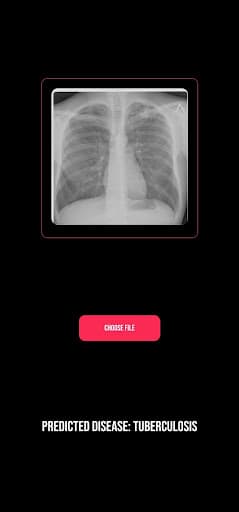

ProjectK is an AI-powered app that can detect pulmonary diseases by analyzing lung X-rays. I made it during a hackathon.

Screenshot 1 of ProjectKScreenshot 2 of ProjectKScreenshot 3 of ProjectKScreenshot 4 of ProjectKScreenshot 5 of ProjectKScreenshot 6 of ProjectK